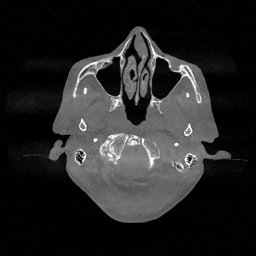

The results for simulated noisy data are shown in Fig. 2. The first and third rows display two representative slices from the test set, and the second and fourth rows present the corresponding error maps. The traditional WCE method suppresses cupping artifacts and recovers some missing anatomical structures but still shows noticeable deviations from the ground truth. Predictions from the four diffusion-based models demonstrate a markedly improved ability to restore anatomical structures. Among them, cDDPM fails to fully reconstruct the patient bed and retains residual noise in its outputs. This noise is attributable to an incomplete reverse denoising process rather than residual Poisson noise, as evidenced in our noise-free experiments (Fig. 5 in the Appendix). PatchDiffusion, diffusionGAN, and I2SB achieve similar visual quality, with I2SB producing the cleanest and most consistent reconstructions.

The experimental results on clinical head data are shown in Fig. 4. The reference images were reconstructed using the fast iterative shrinkage-thresholding algorithm (FISTA) with total variation regularization from non-truncated projection data. In the WCE reconstructions (Fig. 4(b)), severe truncation prevents accurate recovery of anatomical structures outside the FOV. Despite being trained solely on simulated data with a domain gap, all deep learning models can restore a substantial portion of the missing anatomy. Among them, the diffusion-based methods recover soft-tissue boundaries more faithfully than the conventional deep learning approach FBPConvNet, highlighting their stronger image generation capability. However, cDDPM reconstructions exhibit more noticeable noise than those from other methods, consistent with the simulated data results. The patchDiffusion model introduces artifacts within the FOV, likely due to its patch-wise processing strategy. While I2SB shares the same limitations as other diffusion models in perfectly restoring soft-tissue detail, it produces fewer residual noise patterns and fewer artifacts within the FOV boundaries. Overall, Fig. 4 demonstrates the strong efficacy of I2SB in reconstructing real CBCT data.